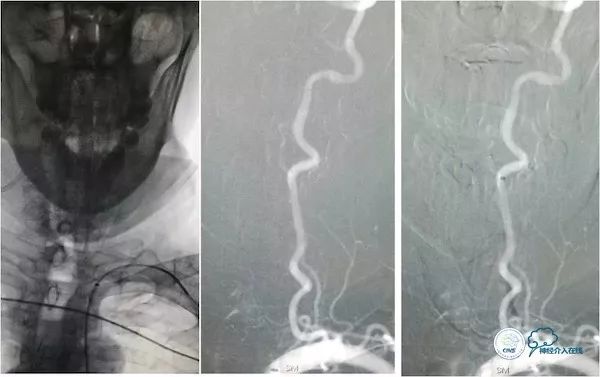

全麻下右股动脉入路,放置7F长鞘(70cm)置于左锁骨下动脉近端,沿长鞘送入5F Navien导管(115cm)至左椎动脉V2段远端(图13)。

图13

造影示基底动脉中下段重度狭窄,近端狭窄可见局部斑块掀起,类似夹层样改变(图14)。

图14

路径图下将Traxcess微导丝(0.014”,200cm)在Echelon-10辅助下放置在右大脑后动脉P2段,交换送入Transend微导丝(0.014”,300cm),沿微导丝送入Gateway(2.0mm×15mm)球囊预扩张(图15)。

图15

后更换Select Plus微导管至右侧大脑后P2段,沿微管送入Enterprise自膨式支架(4.5mm×37mm),到位后释放,造影示:支架贴壁良好,前向血流TICI3级,残余狭窄约30%(图16)。

图16

术后查体同前,术后即刻复查头颅CT未见出血。术后复查头颅CTA示基底动脉支架内通畅(图17)。

图17

灌注CT示后循环低灌注区较前改善(图18)。

图18